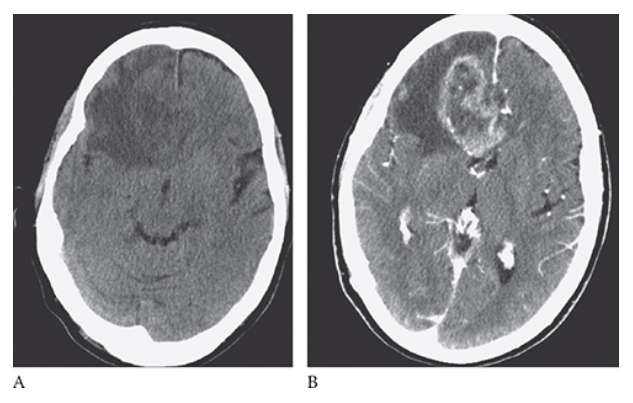

What is A

Glioblastoma Multiforme. Pre-axial CT images show a large peripherally enhancing centrally necrotic mass in the right frontal lobe which is extending across the white matter tracts of the anterior corpus callosum. Note the surrounding edema and mass effect resulting in midline shift.

What is B

Glioblastoma Multiforme. postcontrast axial CT images show a large peripherally enhancing centrally necrotic mass in the right frontal lobe which is extending across the white matter tracts of the anterior corpus callosum. Note the surrounding edema and mass effect resulting in midline shift.